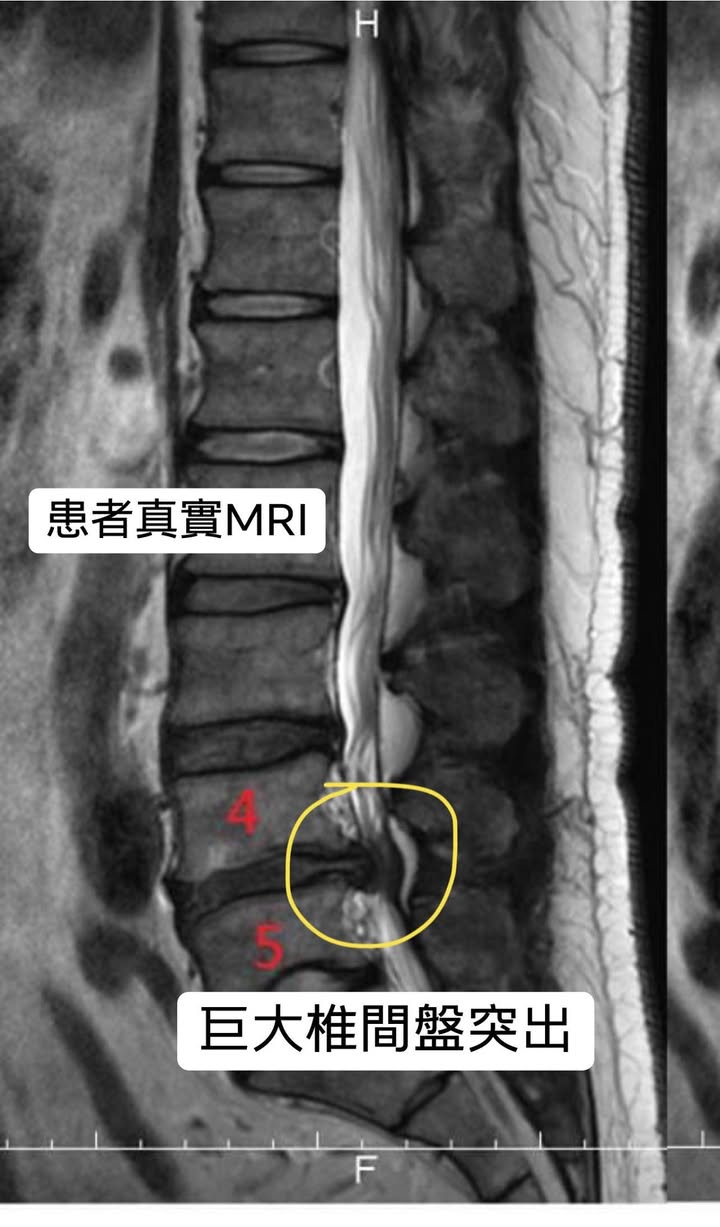

⭕️個案王先生抱怨從109年下半年開始腰痛,疼痛性質麻痛,於當地中醫診所做過傳統針炙3周,也在骨科復健做過電療4周、於振興醫院打過消炎止痛類固醇針1次,晨起最痛,整天不定時疼痛,日常生活誘發麻痛的姿勢久坐久站大約10分鐘就開始痛、走路很少可以超過10分鐘、患者自訴疼痛測量表來看約8分的疼痛,於1/28大醫院安排核磁共振,發現L4/L5明顯椎間盤突出,因為已經嚴重影響生活品質,整天都要吃止痛藥,原本預定於過年開刀,之後經友人介紹來門診諮詢

🎦真實訪問摘錄:2/10~4/24,總共15次治療,第4次治療後麻的感覺少了快一半,疼痛開始顯著下降,之後每次都有改善,在為期九周的治療後,患者表示可以不用開刀是一件很方便的事情,目前走路跟運動都比以前改善太多了